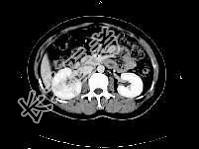

- 单项选择题女,27岁, 寒战高热、尿频、尿痛3天,尿检: 白细胞(+++),CT平扫及增强扫描如图所示, 下列说法错误的是 ( )

A、右肾体积增大

B、增强后右肾实质内可见条片状密度减低区

C、左肾未见异常

D、考虑为急性肾盂肾炎

E、考虑为慢性肾盂肾炎